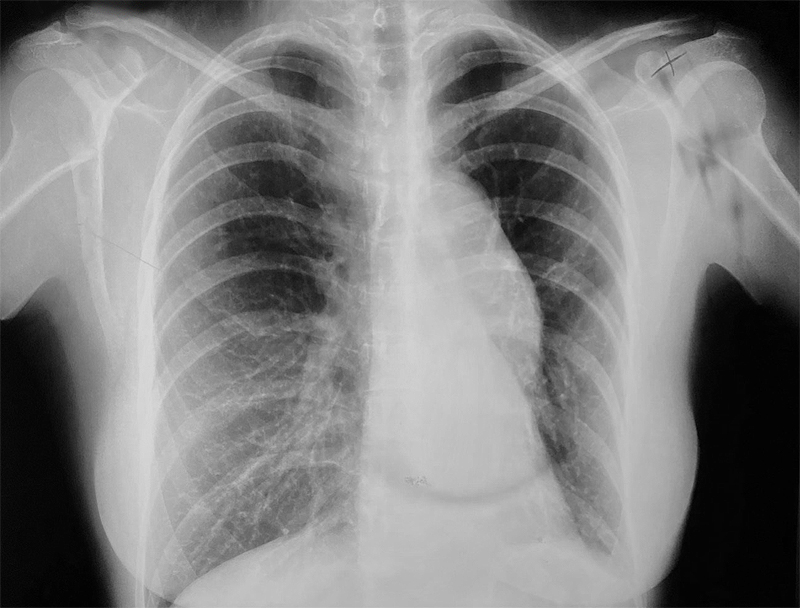

At Saint John’s Health Center, we will perform an X-ray to see if there is an abnormality. If there is an abnormality visible on the X-ray, we will do a CT scan (computed tomography) or MRI (magnetic resonance imaging) scan to gain additional information about the chest wall abnormality, such as size and location. These scans provide additional detail including soft tissue structures.

- Chest X-rays

- CT scans may be used to identify inflammation in areas of the chest.

- Chest x-ray

- CT scan of the chest

Diagnosis of rib fractures is achieved via X-Ray, CT scan, or MRI, which can also look at the organs and soft tissues around the ribs to detect damage to these areas. Most non-displaced fractured ribs heal without surgery in one to two months and are treated with non-surgical care that ranges from aggressive pain management to proper ventilation. For patients with displaced fractures, flail segments, or high narcotic requirements surgical treatment with rib plating may be required along with aggressive pain management and proper ventilation.